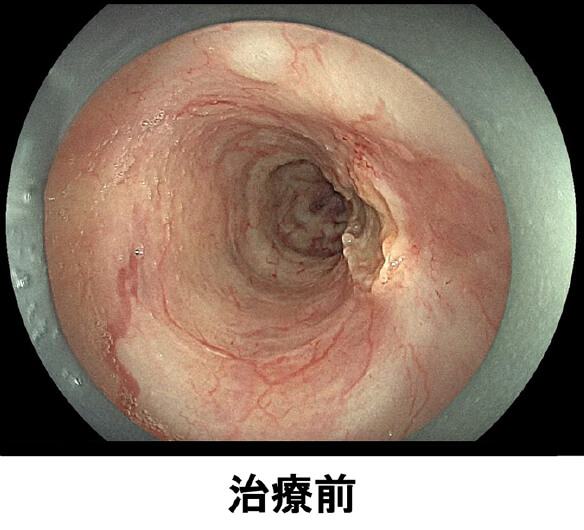

治療前

PDT